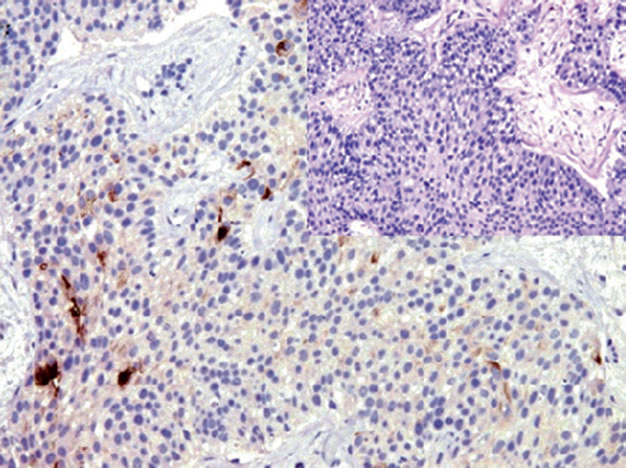

Figure 1. Uroplakin shows positive expression in transitional cell carcinoma.

Figure 2. Transitional cell carcinoma, showing nuclear positive expression of GATA-3.

Figure 3. High-grade transitional cell carcinoma of the bladder,showing CD141 positivity.